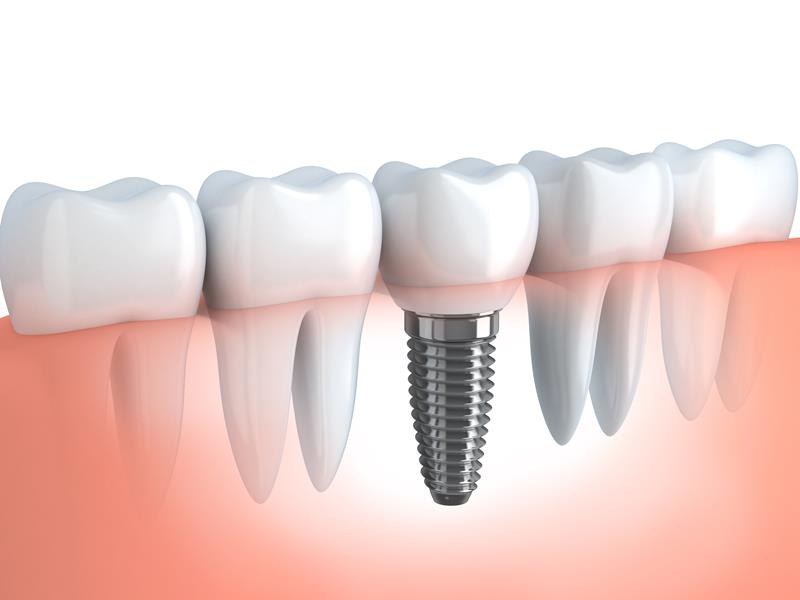

Dental Implants

When you have missing teeth, an alternative solution to dentures is dental implants. While dentures are removable, dental implants provide permanent new teeth to restore your mouth’s function and appearance. Dental implants tend to offer a successful and lasting solution to the loss of some or all of your teeth.